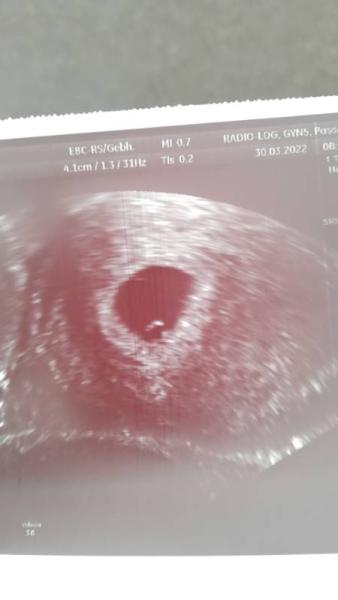

Hallo ihr Lieben, es ist meine erste Schwangerschaft und mir stellt sich die Frage, ob bei noch jemandem dem Ultraschall in SSW6 so aussah wie bei mir. Meine Gynäkologin meint, dass man eine Fruchthöhle erahnen kann, dort wo sich das Kreuzchen befindet. Ich wäre so dankbar für ein paar Rückmeldungen von euch. LG Johanna

Bei mir hat man auch lange nichts gesehen. Im Endeffekt sollte man erst in der 8.SSW zum Arzt. Vorher wird man nur verunsichert. Ich war bei 5+6 beim Arzt, weil der Arzt es so wollte. Und man sah Embryo, Fruchthöhle und Dottersack, aber keinen Herzschlag. Hat mich nur verunsichert. Aber das sieht sehr nach Fruchthöhle aus

Das sieht eindeutig aus wie eine Fruchthöhle :).

ich tippe, dass unterhalb des Kreuzes die fruchthöhle ist und meine auch schon den Dottersack zu erahnen. Viel Glück, dass alles gut klappt. Aber das ist leider die negative Seite, wenn man so früh beim US war du brauchst jetzt viel Geduld in 2 Wochen weißt du mehr. Frühe Termine bringen oft Verunsicherung …